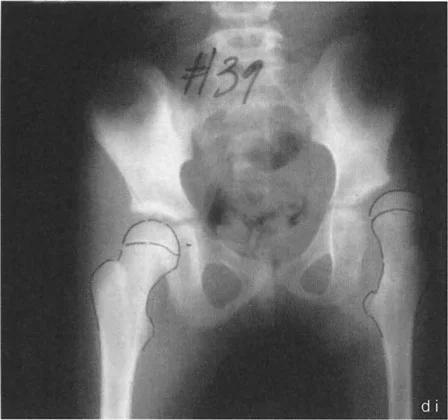

• الورك الفحجاء (Coxa Vara): تشوه يتميز بانخفاض زاوية عنق الفخذ (NSA) إلى أقل من 120 درجة، مما يجعل عنق الفخذ أكثر أفقية. يمكن أن تكون خلقية أو مكتسبة (مثل انزلاق المشاش الرأسي الفخذي SCFE).

* الأشعة السينية (X-rays): هي الخطوة الأولى والأكثر شيوعًا. توفر صورًا مفصلة للعظام وتسمح بقياس الزوايا المهمة مثل زاوية عنق الفخذ (Neck-Shaft Angle - NSA) وزاوية محاذاة الفخذ القريبة (Proximal Femoral Alignment Angle - PFAA).

يستخدم الدكتور هطيف قياسات دقيقة من الأشعة السينية لتحديد مدى التشوه:

* زاوية عنق الفخذ (NSA): الزاوية بين عنق الفخذ وجسم عظم الفخذ. تُشير قيمها المنخفضة إلى الورك الفحجاء، والعالية إلى الورك الروحاء.